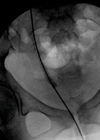

Case 1 A 43-year-old lady presents with urinary incontinence and vaginal pain associated with intercourse. An initial CT scan is performed. Case courtesy of Radswiki, Radiopaedia.org, rID: 12056. Case courtesy of Radswiki, Radiopaedia.org, rID: 12056 What is the clinical diagnosis...